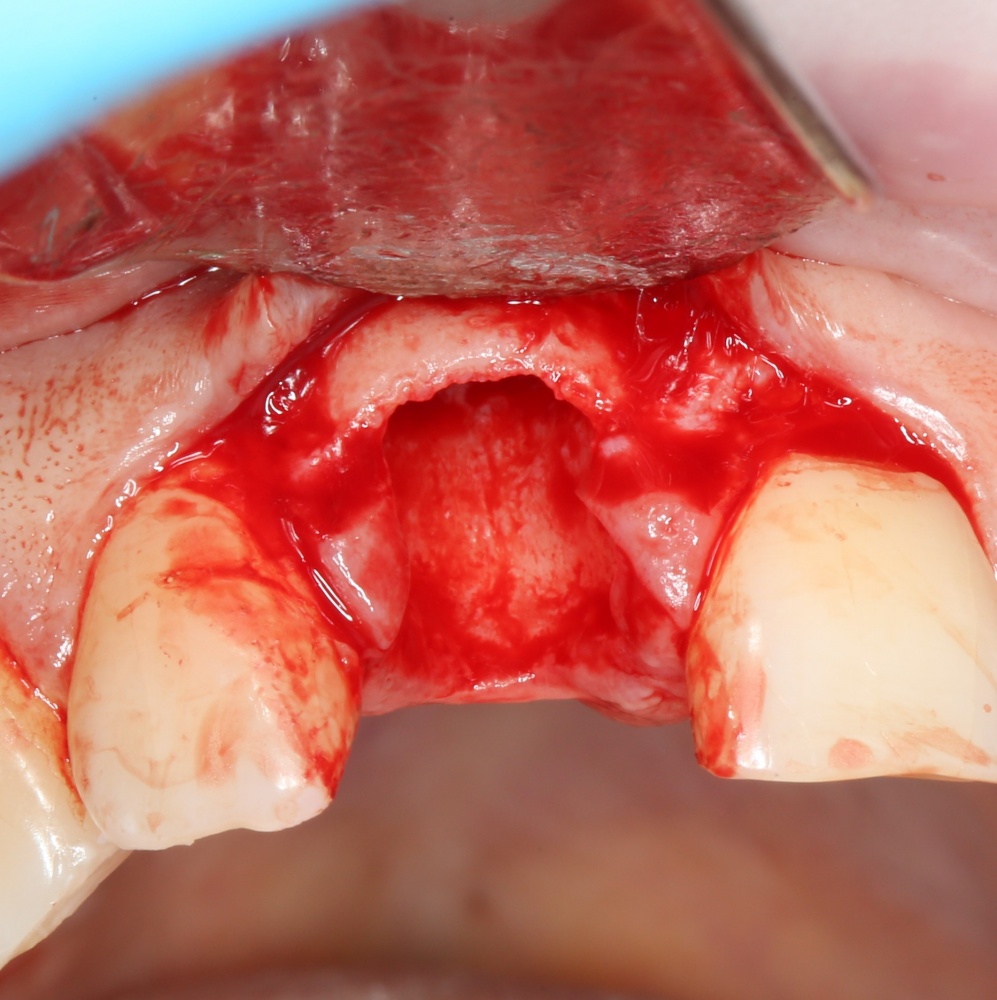

После удаления зуба и сопутствующей гранулемы, остается большая по размеру лунка с тонкой и поврежденной воспалительным процессом вестибулярной стенкой:

Первым делом, необходимо определиться с подготовкой лунки под имплантат. Проверить правильность позиционирования лунки можно с помощью аналогов имплантов, входящих в комплект XiVE Dentsply Implants: